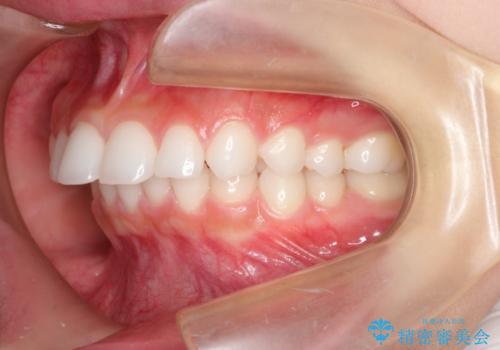

出っ歯の矯正治療 歯を抜かずにインビザラインで

- インビザラインで出っ歯を治したいとの希望がありました。

上顎の歯を全体的に後方に移動させて前歯を引っ込める計画としました。

インビザラインで目立たずに、痛みも少なく矯正治療を終えることができ満足していただけました。